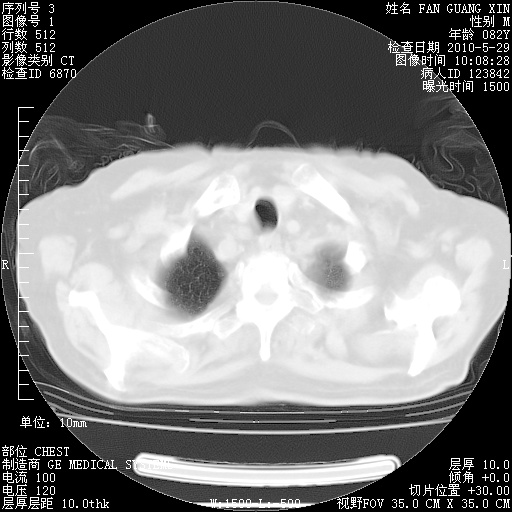

再治疗10天后的肺部CT

肺部体征:呼吸25次/分,心率100次/分,呼吸音增粗。无干湿罗音。

从白细胞总数和中性比例看好像合并感染。肺部纹理好像比上次多,支气管炎?其他感染?

阅读此次胸部CT,肺间质渗出性改变较入院时有吸收。目前从体温、白细胞、中性分叶明显增高,肯定存在细菌感染(发生医院感染哦,若无消化道及泌尿系统等感染的依据,肺部感染可能大)。若你院头孢哌酮舒巴坦钠耐药率较高,同意你的方案,若48小时体温仍高,可考虑使用碳青霉稀类抗菌药物,同时可予超声雾化、注意滴数时加大液体量。白蛋白33.30g/L较低哦,需加强营养等支持治疗。